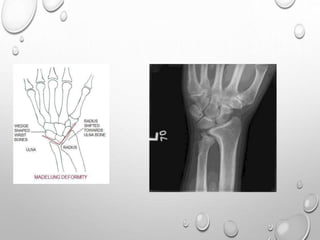

MADELUNG DEFORMITY

DYSCHONDROSTEOSIS

FEMALE

MESOMELIC LIMB SHORTENING

HYPOPLASTIC FEBULA